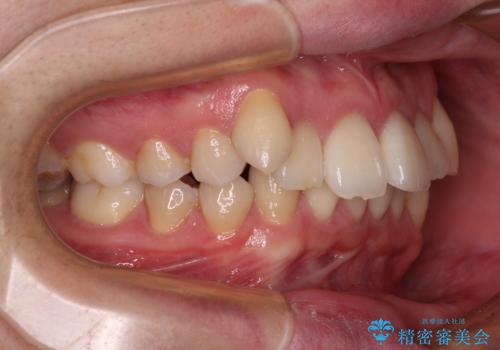

- 前歯のデコボコや八重歯を気にして来院された患者様です。

左右ともに奥歯の咬み合わせに問題があり、上顎臼歯が前方位にある状態で、結果として上顎前歯全体が前方位かつ叢生になっていました。

また、左右ともに上顎最後臼歯が頬側に転移していたため、補助装置を用いて舌側に移動をさせながら、上顎前歯を引っ込むように移動させることとしました。

口元の突出感を解消させるため上顎左右第一小臼歯2本を抜歯して、ワイヤー装置にて矯正治療を行うこととしました。